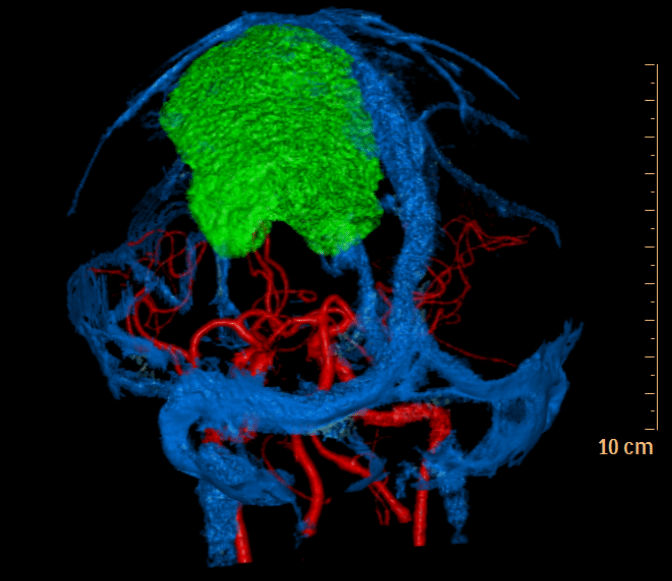

辗转多家医院后,苏先生带着最后的希望,来到我院神经外科。入院后进一步检查发现,这颗“拳头”已经压迫并侵袭了脑部重要的静脉血管——上矢状窦。神经外科千超主任医师、张毓主任医师及李海马博士团队迅速评估后指出,若不及时手术,肿瘤及周围水肿面积会继续扩大,最终将导致右侧肢体永久性偏瘫。开颅肿瘤切除术,是解除压迫、根治疾病的唯一选择!

手术一切准备就绪,监护仪在滴答作响。无影灯下,千超主任凝神静气,手中的显微器械在方寸之间精准游走。手术的最大难点在于,肿瘤与脑组织、静脉窦粘连极紧,像树根盘绕在岩石上。分离时必须极尽仔细,稍有不慎,就可能引发大出血或是瘫痪。

团队采用显微外科技术,沿肿瘤边界层层推进、毫米级剥离。从清晨到午后,历时8小时,最后一缕瘤体被完整取下,所有人悬着的心才稍稍放下。术中出血控制理想,重要静脉窦完好保留。术后病理回报:良性脑膜瘤(WHO 1级)。